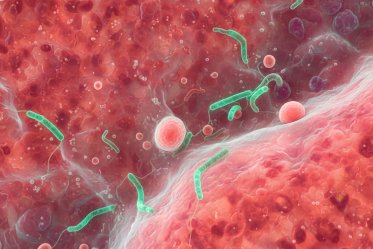

Внутрипечёночный холестаз беременных — это заболевание печени, которое может возникнуть только во время беременности. Холестаз приводит к выработке организмом большего количества желчных кислот. Он может вызывать сильный зуд кожи без сыпи, но проходит после рождения ребёнка.

- Высокий уровень желчных кислот.

- Повышение уровня гормонов беременности, замедляющих отток желчи.

Внутрипечёночный холестаз встречается при беременности, а также как самостоятельное заболевание и как симптом хронического заболевания гепатобилиарной системы. ВХБ носит семейный характер и развивается у близких родственников (матерей, дочерей и сестёр).